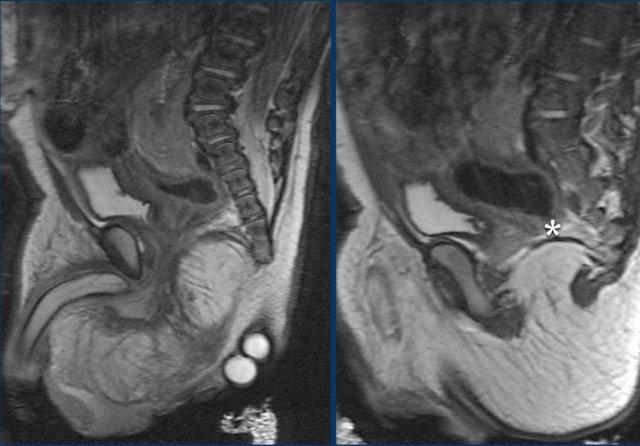

Teo hậu môn

Chẩn đoán teo hậu môn thường rõ ràng trên lâm sàng qua quan sát và thăm khám bằng ngón tay.

Teo hậu môn là một phần trong phổ dị tật hậu môn-trực tràng và ổ nhớp, là một rối loạn phức tạp.

Chẩn đoán hình ảnh và điều trị cần được thực hiện tại các trung tâm chuyên khoa.

Ban đầu có thể sử dụng phim X-quang thường và siêu âm để xác định vị trí của dị tật và đánh giá nhu cầu làm hậu môn nhân tạo.

Ở giai đoạn muộn hơn và trước khi phẫu thuật triệt để, sự kết hợp giữa các nghiên cứu chiếu chụp dưới màn tăng sáng và MRI sẽ được sử dụng để mô tả giải phẫu phức tạp của các cấu trúc hậu môn-trực tràng, tiết niệu-sinh dục, vùng chậu và tầng sinh môn cũng như các đường rò liên quan.

Teo hậu môn là một phần của nhóm dị tật VACTERL và bệnh nhân cần được tầm soát các dị tật đi kèm.